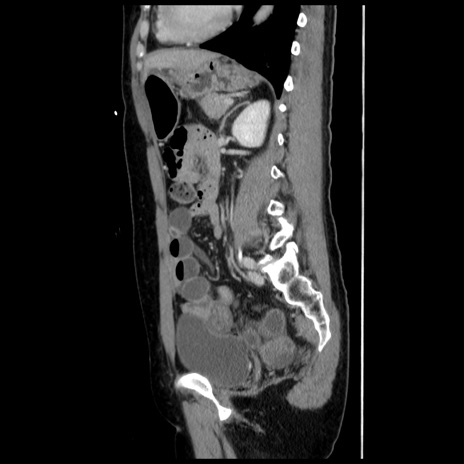

横断像